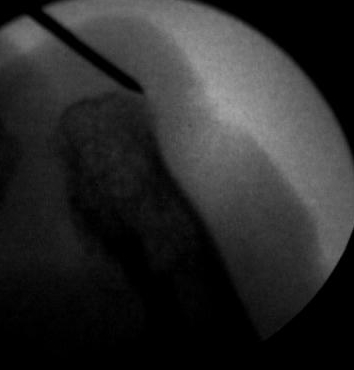

Ante un cambio en la forma y coloración de la uñas, lo primero que pensamos es que puedan ser «hongos» pero en la gran mayoría de los casos el problema está «en el interior». La uña está engrosada, puede tener alguna grieta, cambio de color y además puede ser dolorosa a la presión del calzado. Ese aspecto de «uña fea» puede ser a consecuencia de la malformación o del mal crecimiento del hueso que hay en el interior del dedo y que da lugar a esta malformación de la uña debido a que este hueso invade el territorio de todo el aparato ungueal. Digamos que la uña en vez de crecer normalmente a lo largo (longitudinalmente) crece a lo alto (verticalmente) dando ese aspecto de «uña enferma». Por ello, para un buen diagnóstico es necesario un estudio radiológico donde poder observar esa excrecencia de hueso que dará lugar a ese mal crecimiento de la uña. Las imágenes radiológicas nos van a mostrar ese montículo en el hueso causante de la deformidad de la uña.

La solución a este problema radica en pulir ese exceso de hueso que no permite crecer a la uña con normalidad, eliminando así la presión interior que soporta la uña. El procedimiento que se realiza es mediante Cirugía de Mínima Incisión gracias a la cual pulimos y damos una forma más rectilínea al extremo distal de la falange (hueso implicado) del dedo gordo. Es una técnica muy poco agresiva ya que con tan solo 4mm de corte en la piel podemos llegar al hueso y trabajar en él. Todo bajo anestesia local y sin dolor alguno podemos eliminar el problema «de raíz». El dolor postoperatorio es inexistente y la recuperación rápida e inmediata.